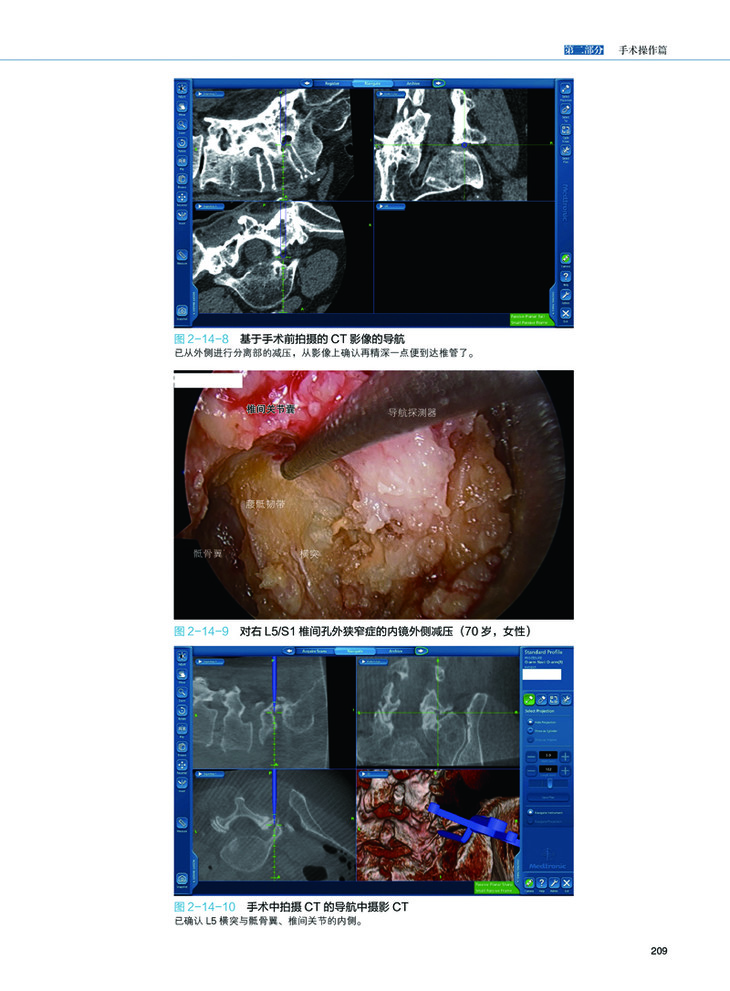

第二部分介绍了椎间盘疝、椎间管狭窄、腰椎变性疾病、椎孔狭窄、囊肿、颈部脊髓疾病、颈部神经根病变、颈椎间盘突出,胸椎病变等疾病的内视镜下手术方法。